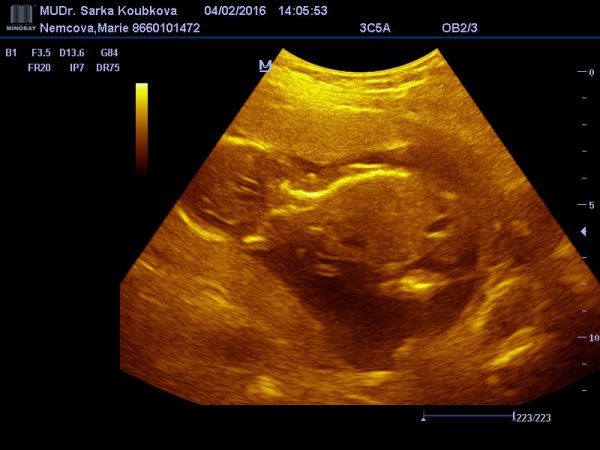

18.týden těhotenství